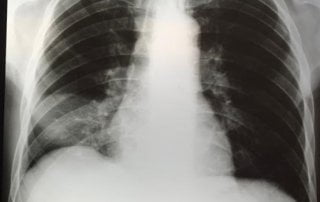

Pneumonia e HIV: Existe alguma relação?

As pessoas que vivem com HIV podem ter diversos tipos de pneumonia. Quanto mais prejudicada a imunidade (ou seja, quanto pior o CD4), maior o risco. Quando o CD4 é bom, o risco é parecido ao das pessoas que não vivem com HIV. Tipos de pneumonia que a pessoa [...]